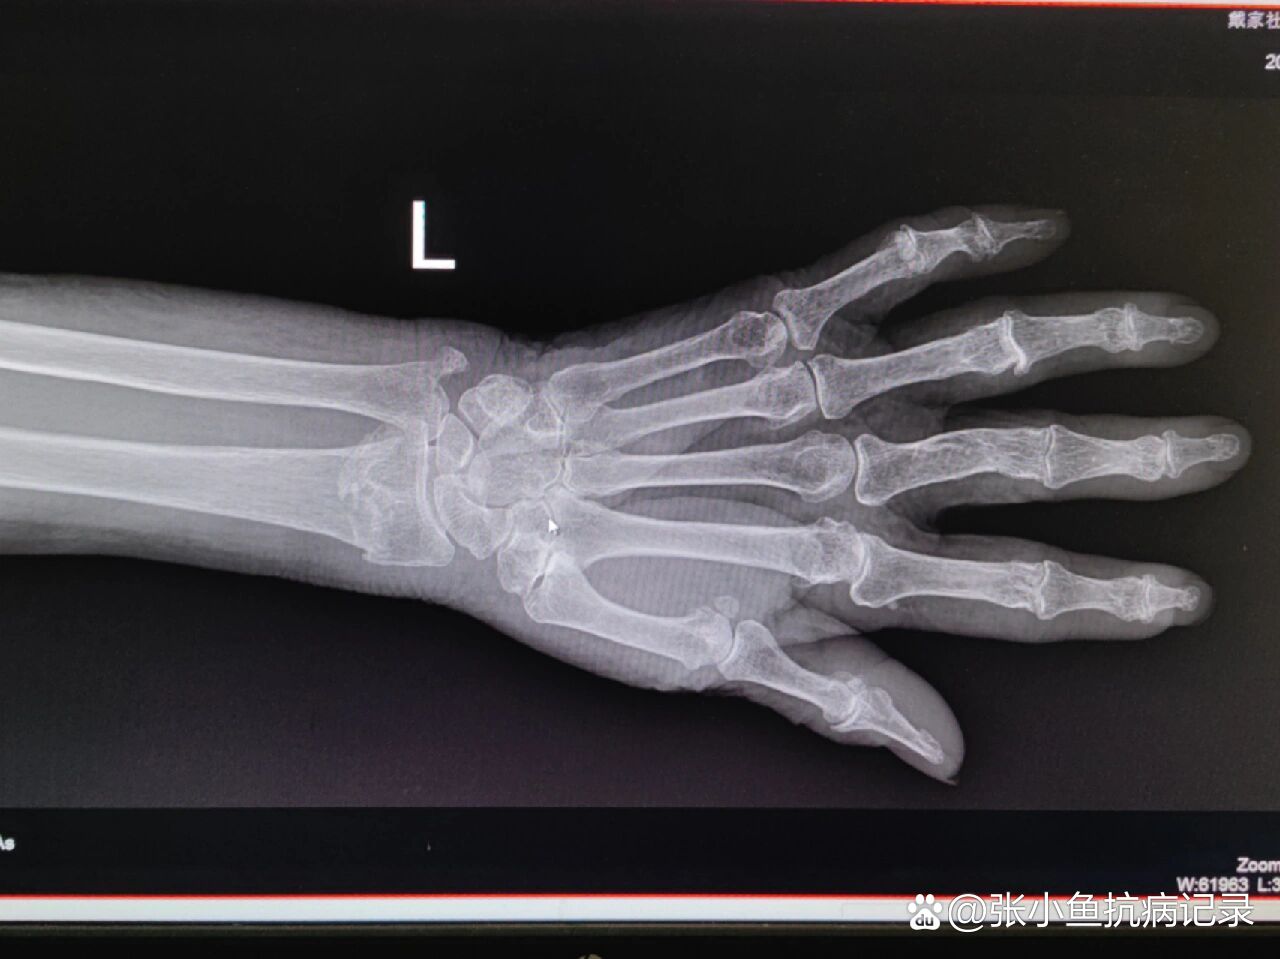

手腕骨折的症状及处理方法如下症状表现1疼痛骨折部位会出现剧烈疼痛,尤其在活动或受力时加重,可能影响手部正常活动2肿胀与淤青受伤部位迅速肿胀,皮肤可能出现淤青,这是由于血管破裂和局部出血所致3畸形手腕可能出现缩短旋转或成角等异常形态,与健侧对比更明显4功能障碍手部活动受限,如握拳伸展手指或旋转手腕;5 X光检查X光是诊断骨折的金标准,可明确骨折类型如横断斜行或粉碎性及位置若症状持续不缓解,即使初期X光未显示异常,也需复查以排除隐匿性骨折特殊情况需注意儿童因骨骼未完全发育,骨折症状可能不典型如仅表现为哭闹拒绝使用手腕,且可能因骨骺损伤影响生长家长需密切观察,若发现;手腕骨折的症状及处理方法如下一典型症状 1疼痛骨折后手腕会出现剧烈疼痛,尤其在尝试移动或受力时疼痛加剧,可能伴随刺痛或灼烧感2肿胀和淤血骨折部位会迅速肿胀,局部皮肤可能出现淤血青紫或发红,这是由于血管破裂和软组织损伤导致的3畸形严重骨折时,手腕形态可能发生改变,如骨头突出;手腕骨骨折的常见症状如下1 疼痛和肿胀骨折发生后,手腕部会立即出现剧烈疼痛,尤其在尝试活动或受力时加剧同时,局部软组织因出血和炎症反应迅速肿胀,可能伴随皮肤温度升高或发红肿胀范围通常与骨折严重程度相关,严重时可波及整个手腕甚至前臂2 畸形骨折端移位会导致手腕外观出现明显畸形,例如;影像学检查可见骨连续性完全中断,骨折端位置异常,多由较大外力撞击或摔倒时手腕撑地等导致症状表现手腕骨裂局部疼痛较轻,肿胀不明显,仅有轻微压痛,手腕活动受限较小,可进行轻度活动但疼痛加重手腕骨折则疼痛剧烈,肿胀明显,可能伴有皮下淤血和青紫色瘀斑,手腕畸形如短缩成角等,活动受限严重。